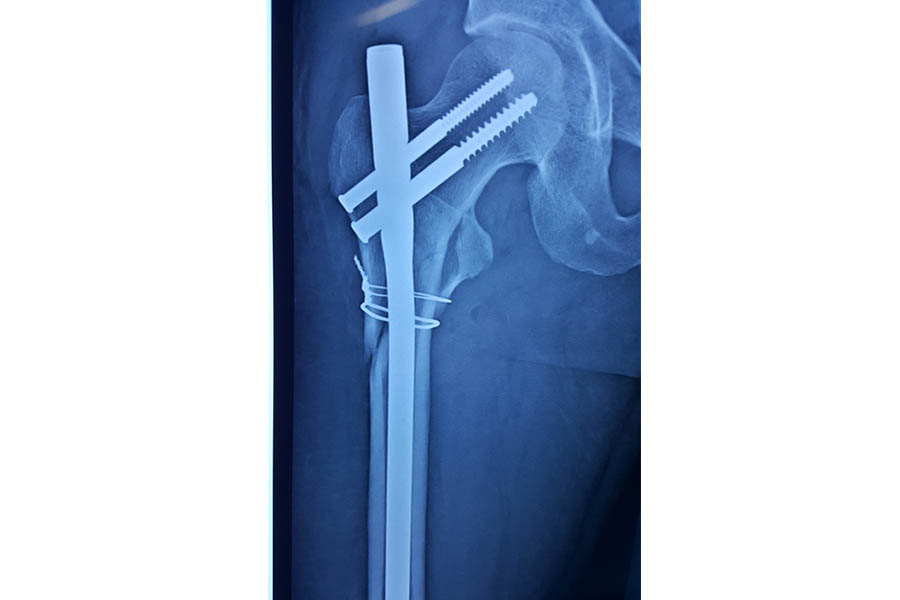

Trauma

Case 1